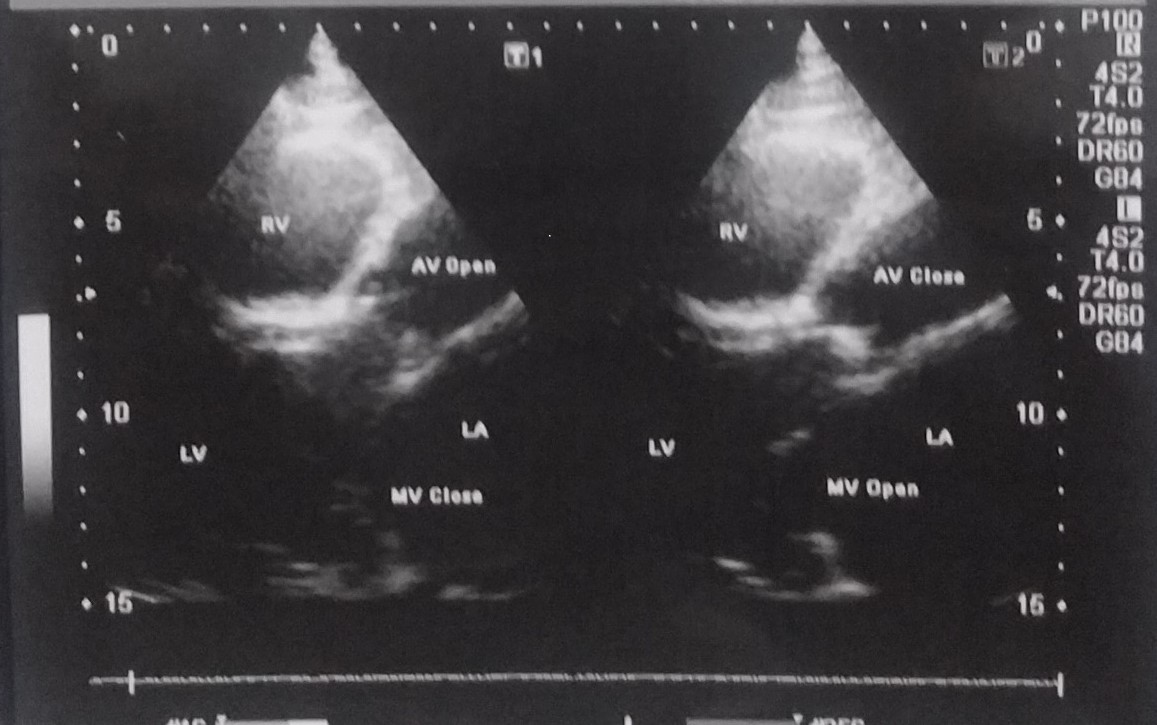

<心臓超音波>

心臓超音波Bモードによる左心室機能評価

左心室機能計測値

左室径短縮率(%FS)0.38 (基準:0.26~0.55)

駆出率(EF)0.67(基準:0.64~0.75)

左心不全では上記のデータはいずれも低下しますが、M.Yさんのデータはいずれも基準範囲でした。